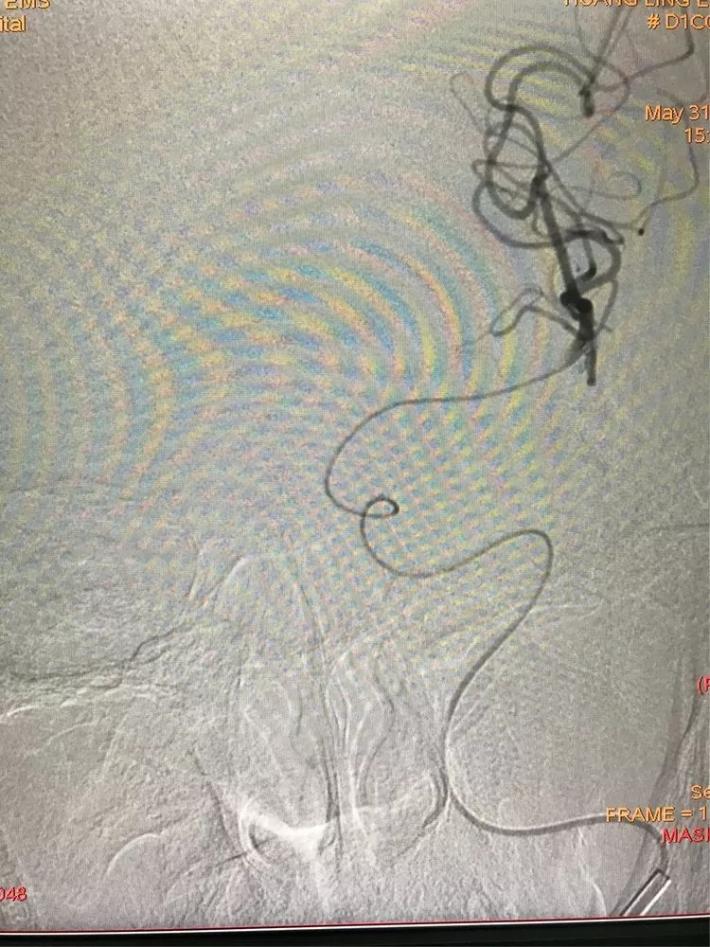

第三次上微导管。

支架打开取栓。

见基底动脉血流恢复,左侧大脑后动脉血流欠佳。